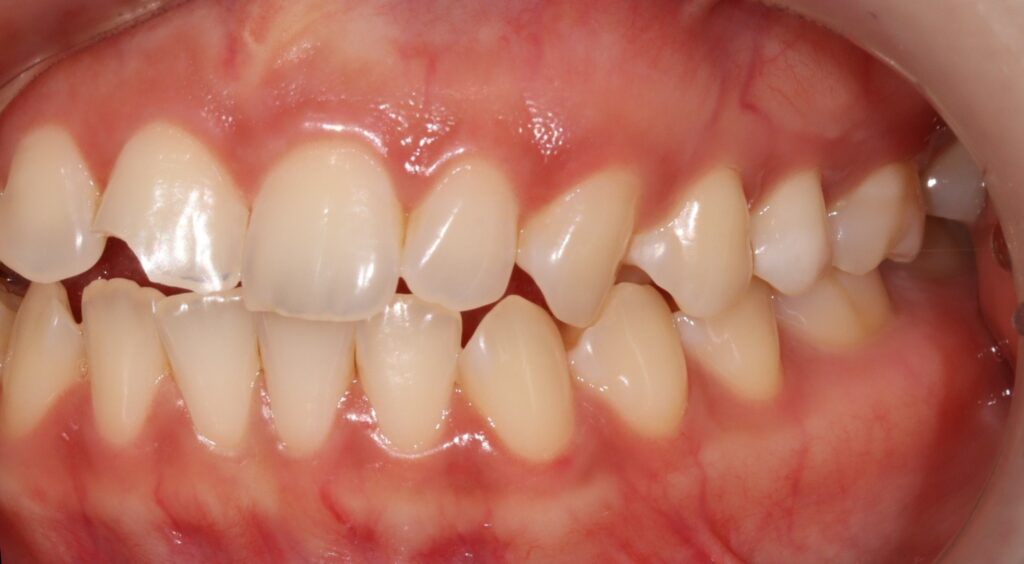

최종 방법,

레진 수복 치료

경과 관찰을 통해 치수가

건강한 상태로 확인되어

레진을 이용한 직접 수복으로

치료를 진행합니다.

레진 치료는 치아를 보존하면서

자연스러운 모습을 재현할 수 있는

장점이 있습니다.

특히 앞니의 경우

심미적인 부분이 중요하므로

절단 부위의 투명도를 재연하는 것이

치료의 핵심 포인트입니다.

여러 가지 색조의 레진을 층별로 쌓아

자연치와 유사한 투명감과

색상을 구현합니다.